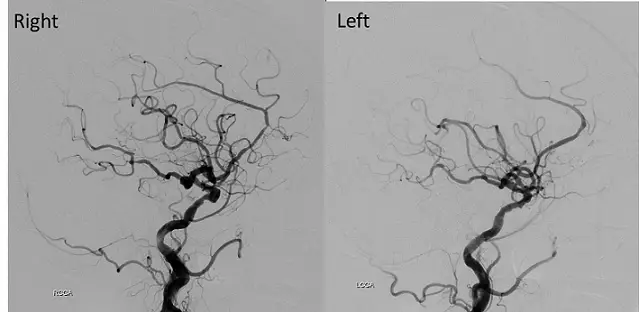

84歲女性,有高血壓病史,突然頭痛噁心而至急診求診。頭部電腦斷層檢查發現有廣泛蜘蛛網膜下腔出血(subarachnoid hemorrhage, SAH)併腦室內出血;進一步做頭部血管攝影檢查,影像如附圖(右側及左側頸動脈造影),造成她SAH的原因最可能為下列何者?

本題聚焦於蛛網膜下腔出血(SAH)最常見的動脈瘤來源位置與血管攝影(DSA)在定位動脈瘤時的影像學特徵。考生須能判讀左右側頸動脈DSA影像,辨識出在哪一側、哪個動脈分叉或分支處出現囊狀突出,進而對照常見出血源──特別是ICA和PComA交界處的動脈瘤。

從右側內頸動脈(ICA)DSA的側位及前後位影像可見:

- 在ICA遠端與Posterior communicating artery(PComA)起始處,動脈壁突起一個小而明顯的囊袋樣結構,形狀為圓形至橢圓形,且頸部清晰可見,指向後內側方向,符合典型ICA–PComA交界動脈瘤(saccular aneurysm)影像學特徵(insightsimaging.springeropen.com)。

- 同一平面下,左側ICA注射則未見類似囊袋(aneurysmal sac)突出,血管走形連續光滑。

出血CT所示廣泛SAH伴腦室出血,與動脈瘤破裂後高壓血液流入蛛網膜下腔及側腦室吻合。PComA動脈瘤破裂時常見基底池大量出血,並可累及第三腦神經引發局部神經症狀,但此題主要根據DSA定位。